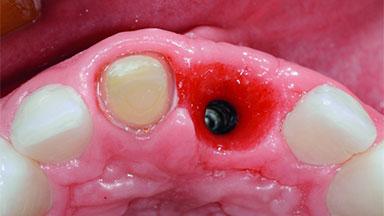

Replacement of an Ankylosed Upper Left Central Incisor: Bone Augmentation and Socket Grafting, Late Placement of an RC Bone Level Implant

Placement Protocol Early or late implant placement

Bone Volume Deficient horizontally, requiring prior grafting